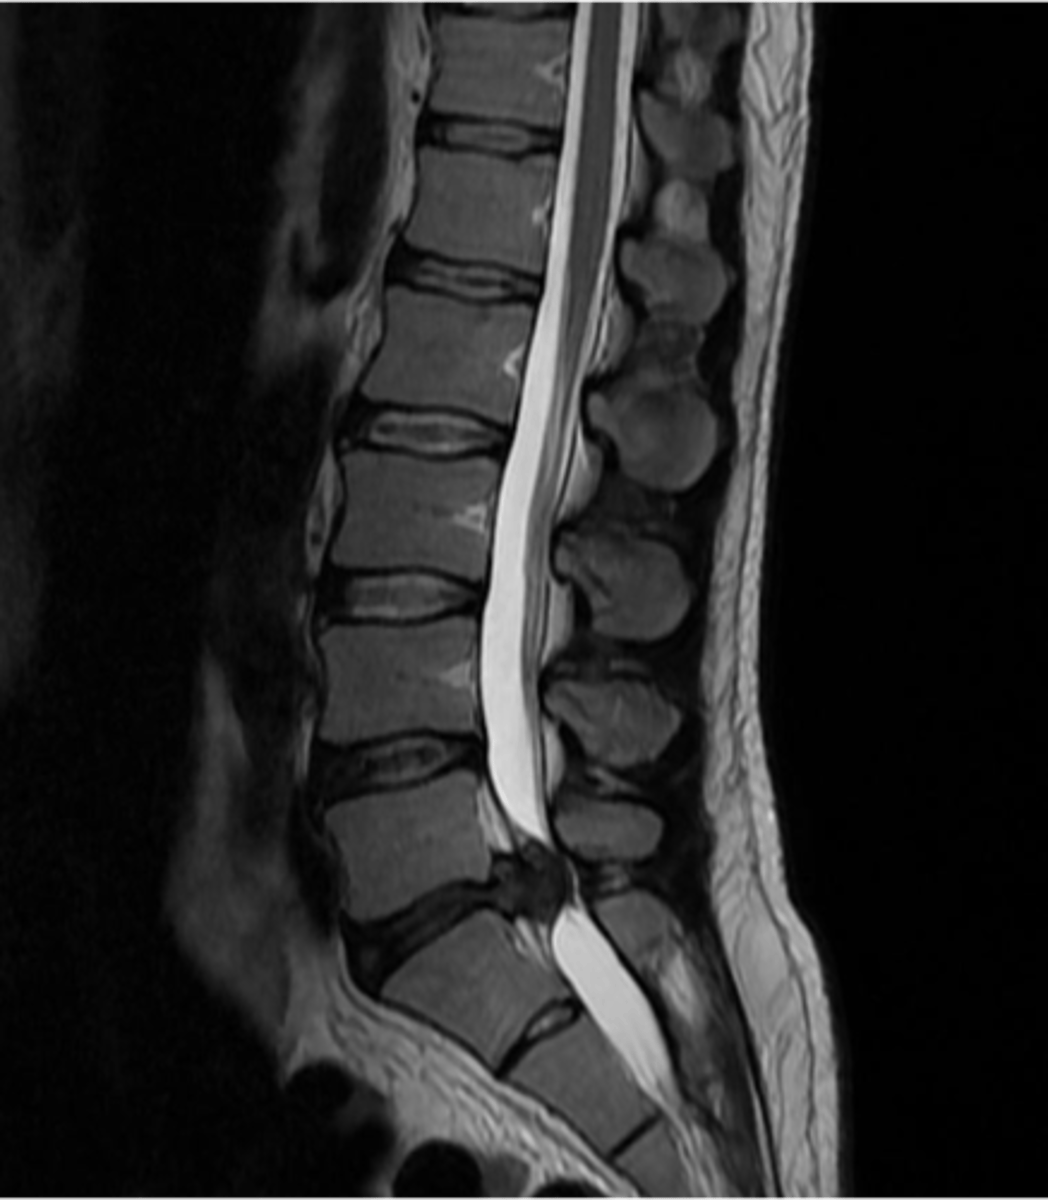

spondylolisthesis

forward slipping of one vertebra over another (caused by vertebral fracture at the pars interarticularis)

spondylolithesis can be caused by ____ or ______

degenerative or traumatic etiology

spondylolisthesis s/s can range from none to _______

severe low back pain with radiculopathy